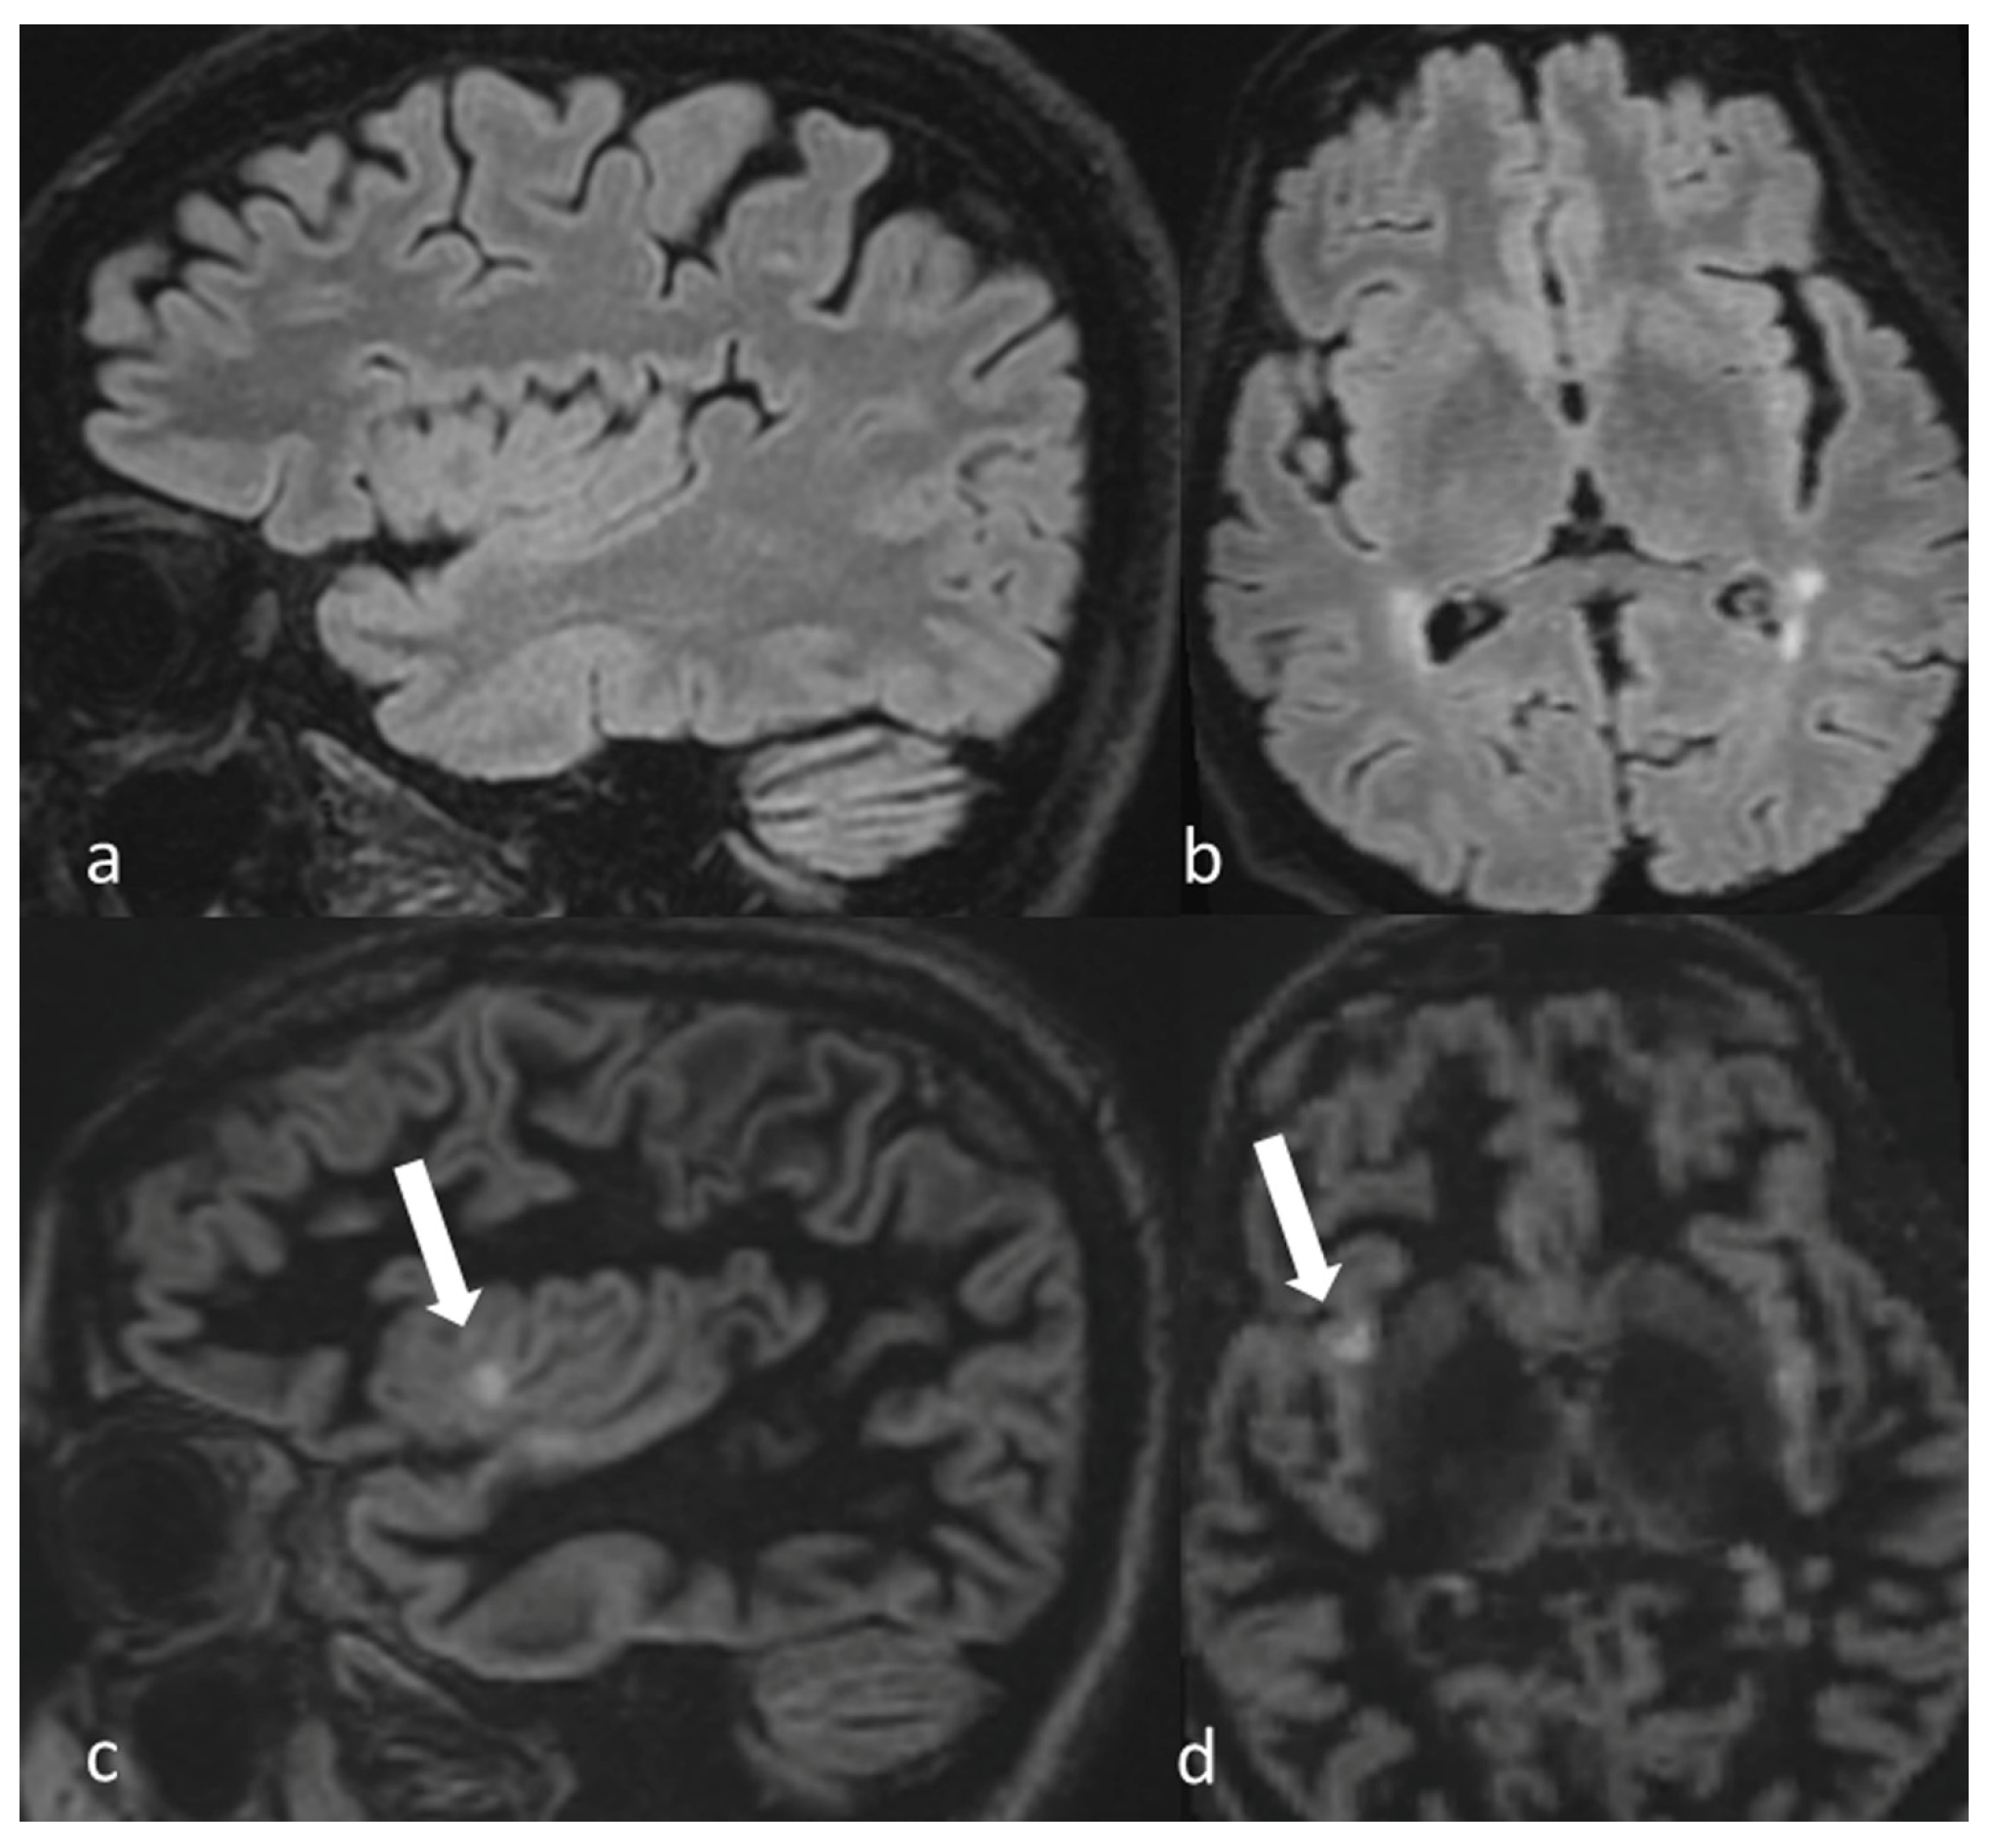

| Practical Recommendation |

| In MS protocol, attention has to be paid to perform DIR before contrast-administration, as post-contrast DIR may suppress active subcortical lesions. |